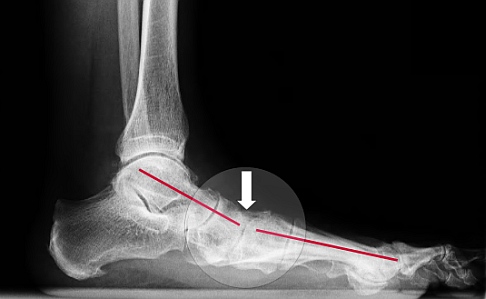

Beim Knick-Senkfuß ist das Fußlängsgewölbe (rot) am Scheitelpunkt eingesunken (Pfeil). Der Knick-Senkfuß ist besonders bei älteren Patienten eine häufige Ursache für Fußschmerzen. © Gelenk-Klinik

Die Knick-Senkfuß-Fehlstellung führt zu einem Absinken des Fußlängsgewölbes. Die Zehen weichen dabei nach außen ab. Bei Erwachsenen ist die Ursache des Knick-Senkfußes meist eine geschwächte Tibialis-posterior-Sehne (hinterer Schienbeinmuskel). Sie leistet einen entscheidenden Beitrag zur Stabilisierung des Fußlängsgewölbes. Ist sie verletzt oder geschwächt, kommt es zu Fußschmerzen auf der Innenseite und am Innenknöchel. Der erworbene Knick-Senkfuß tritt meist im Alter von 40–50 Jahren erstmals auf und kann unter Belastung sehr schmerzhaft werden.